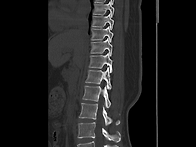

척추CT영상의 일부분입니다..

엉치아파 25.07.1710일전 교통사고나서 입원후에골절은 없다고 설명 듣고는 2주진단받고..